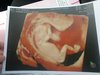

A to moje maleństwo z pn (12+3), dxidziol nie chciał współpracować.. Wykryto Arse, za 3 dni następne usg genetyczne.

Załączniki

• IMG_20200217_120347.jpeg

IMG_20200217_120347.jpeg

45,7 KB · Wyświetleń: 113